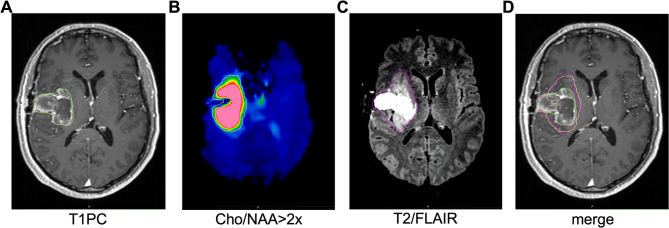

Methods: Patients with pGBM (n = 18) and rGBM (n = 19) underwent sMRI with RT simulation. T1-post contrast (T1PC) and T2/FLAIR MRI volumes were contoured. sMRI generated choline/N-acetylaspartate > 2x (Cho/NAA > 2x) volumes are known to correlate with high-risk invasion. Hausdorff distances were calculated to define the margin necessary to cover Cho/NAA > 2x in pGBM and rGBM. In rGBM, mock CTV expansions from T1PC volumes were created to determine non-selective CTV expansion sizes needed to cover Cho/NAA > 2x volumes.

Results: For pGBM, the median T1PC, Cho/NAA > 2x, and T2/FLAIR volumes were 32.3 cc, 45.0 cc, and 74.8 cc respectively. For rGBM, the median T1PC, Cho/NAA > 2x, and T2/FLAIR volumes were 21.7 cc, 58.9 cc, and 118.3 cc, respectively. T2/FLAIR volumes increased more relative to T1PC volumes in rGBM than pGBM (p ≤ 0.001). Meanwhile, the median Hausdorff distance between T1PC and Cho/NAA > 2x was 22.9 mm in pGBM and 25.7 mm in rGBM, suggesting that the high-risk volume does not significantly change. In rGBM, it is common to use no CTV expansion from the T1PC volume which only included 61% of high-risk Cho/NAA > 2x volume. Conversely, T1PC expansions of 10-, 15-, and 20-mm covered 87%, 94%, and 98% of Cho/NAA > 2x volume.

Conclusions: sMRI Cho/NAA > 2x delineates high-risk occult disease in glioblastoma and extends beyond T1PC MRI borders. Typical large CTV expansions in pGBM mostly include Cho/NAA > 2x volumes. However, small CTV expansions commonly used in rGBM poorly cover Cho/NAA > 2x, suggesting that larger CTV expansions or Cho/NAA > 2x guidance may be of benefit.